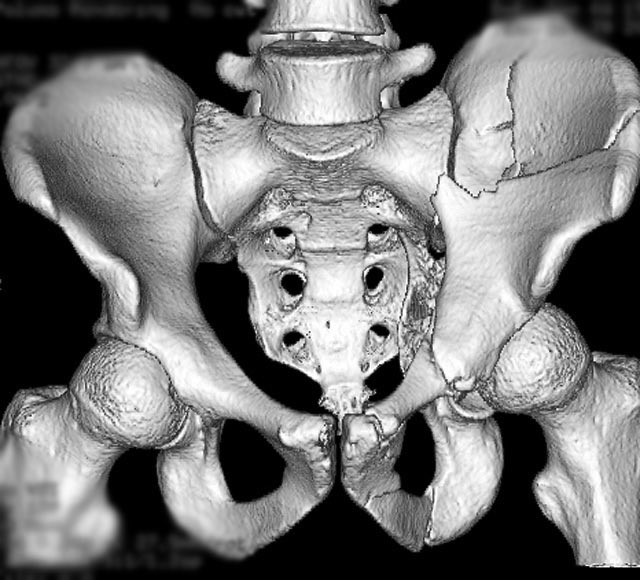

Isolated injury in a 38yo male driver after an automobile crash - can you identify the radiographic lines and fracture pattern?

The surface rendered CT helps “to see” the AP plain film better